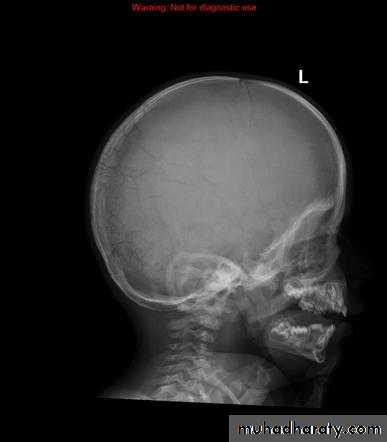

Wormian bone

What is it being ??? Wormian bone are a subset of the small intra sutural bones that lie between the cranial sutures mainly seen around the lambdiod suturesCauses ?????

osteogenesis imperfecta

rickets

cleidocranial dysostosis

Hypothyroidism

Down syndrum